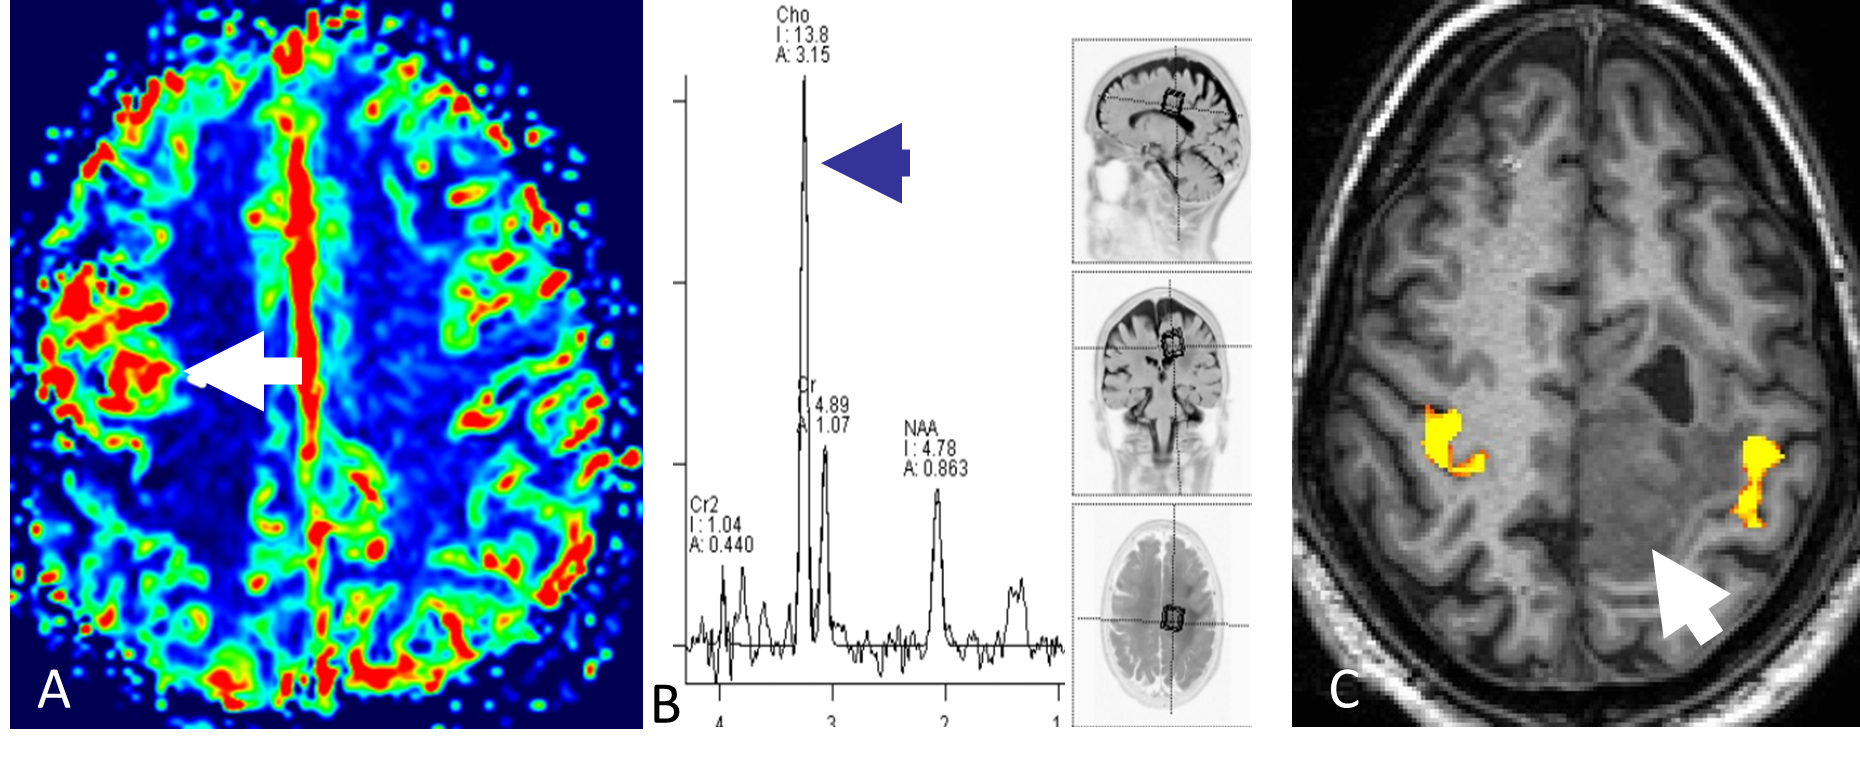

Ved å gi en rask intravenøs injeksjon med kontrastmiddel og deretter følge kontrastens passasje gjennom kapillærsirkulasjonen i hjernen, kan man ved MR-perfusjon få informasjon om variabler som blodvolum og blodperfusjon i hjernevev og tumor. Høygradig maligne svulster har typisk mange og store tumorkar og har derfor høyere blodvolum og perfusjon enn lavgradige svulster (Figur 5.2). MR-perfusjon kan videre differensiere svulster fra andre tilstander, for eksempel vil strålenekrose oftest ha lavt blodvolum og lav blodperfusjon (Mabray et al., 2015).

MRS gir informasjon om biokjemiske forhold i hjerneparenchymet. Hydrogenkjerner har litt ulike MR-egenskaper avhengig av hvilket molekyl de er bundet til. Ved MRS brukes disse små forskjellene til å lage et spekter hvor toppene representerer ulike metabolitter og størrelsen på toppene indikerer konsentrasjonen i vevet. Ved en rekke tilstander endres vevets biokjemi; i maligne svulster øker for eksempel mengden av metabolitten cholin (Figur 5.2) (Mabray et al., 2015). Diagnostisk benyttes metoden særlig til å differensiere mellom ulike hjernesvulster og for å skille mellom tumor og annen type patologi.

BOLD fMRI er en MR-metode som benyttes til kartlegging av hjerneaktivitet. I klinisk sammenheng benyttes BOLD fMRI særlig til å kartlegge viktige kortikale områder før kirurgisk behandling av hjernesvulster (Figur 5.2). Metoden har dessuten fått svært stor betydning i nevrovitenskapen for å øke forståelsen av hjernens funksjoner.